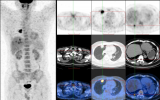

國際頂級機構(gòu)發(fā)布的PET成像指南

FAPI 是一種放射性示蹤劑前體,全稱為成纖維細(xì)胞活化蛋白抑制劑,它通過與FAP結(jié)合,可在PET/CT掃描中精準(zhǔn)可視化各類腫瘤的位置和大小 。自2019年68Ga-FAPI PET/CT影像獲得SNMMI(北美核醫(yī)學(xué)和分子影像大會)的年度圖片以來,全世界對于FAP PET的研究白熱化,涌現(xiàn)了一波又一波高質(zhì)量研究,積累了無數(shù)FAP PET的臨床應(yīng)用經(jīng)驗。2024年11月21日,SNMMI與EANM在世界核醫(yī)學(xué)頂刊《美國核醫(yī)學(xué)雜志》上聯(lián)袂發(fā)布FAP PET的成像指南 ,這標(biāo)志著FAP PET登堂入室,獲得.. 2024-11-25